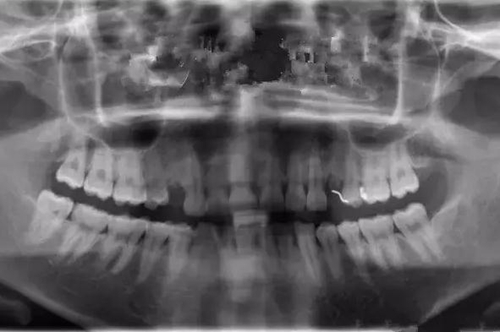

治療之前,先做口腔全景CT片:

從CT片中可明顯看到右側上頜一雙尖牙缺失,但是牙槽骨條件良好、無炎癥,做種植比較簡單、也符合該客戶不傷鄰牙、方便的需求。